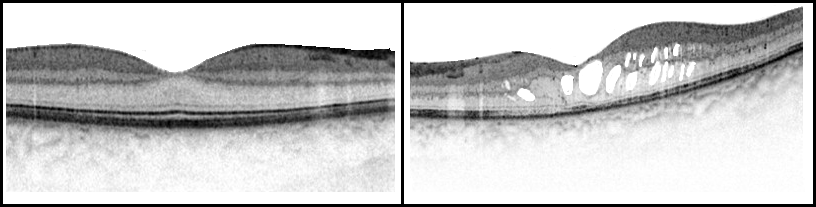

Φυσιολογική Ωχρά Κηλίδα Τομογραφία Οπτικής Συνοχής (OCT Scan) |

Διαβητικό Οίδημα της Ωχράς Κηλίδας Τομογραφία Οπτικής Συνοχής (OCT Scan) |